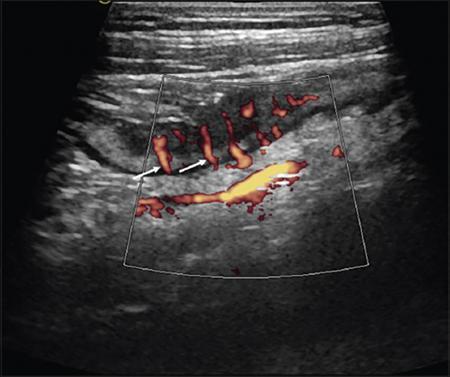

Ultrasonography (USG)

Kulbir Ahlawat, Ravi Chaudhary, Arvind Pandey, Anuj Bahl, Navni Garg, Sonam Shah, Sonali Sharma EMBRIOLOGY AND ANATOMY OF COLON Sonali Sharma A deep understanding of the development and the embryology of the colon is essential to understand the variety of the developmental anomalies related to the aberrations in the normal embryological processes (Table 8.4.1.1). Broadly the development of the colon can be summarized in three stages: The rate of growth of the embryo exceeds the growth rate of the yolk sac during the third and the fourth weeks of development. During the fifth week there is development of the omphalomesenteric duct or the Vitello intestinal duct or the yolk stalk which serves as a connection between the extraembryonic and the intraembryonic coelom (Fig. 8.4.1.1). The midgut at this point is divided into two equal length segments and the loop has its axis at the superior mesenteric artery (SMA). The apex is marked by the yolk stalk or the omphalomesenteric duct. There is a periarterial segment and the postarterial segment of the loop, the former starting at the foregut–midgut junction and ending at the apex. The postarterial segment lies between the apex and the midgut–hindgut junction. Eleventh week marks the beginning of the return of the postarterial segment of the gut, which continues to rotate in front and then to the right of the SMA. By the twelfth week the colon completes a 270-degree anticlockwise rotation with prior 90 degrees during herniation, and a further 180-degree counterclockwise rotation during the reduction of the postarterial segment. The prearterial segment gives rise to: Postpapillary duodenum, jejunum, ileum (major part) The postarterial segment gives rise to: Terminal ileum, caecum, appendix, ascending colon, transverse colon (major part) There is a switch over to the hind gut at the junction of the proximal two-thirds and the distal one-third of the transverse colon where there is also a switch over in the arteries supplying the segments, with SMA (middle colic) supplying the proximal segment and the inferior mesenteric artery (IMA, left colic) supplying the distal segment. The fifth week also marks the development of a small swelling in the proximal postarterial segment which represents the caecal bud. There is the herniation of the midgut at the sixth week of development called the physiological herniation of the gut. At this time there is growth of the liver, and the right lobe pushes the prearterial segment downwards and to the right. The series of events represent a 90-degree counterclockwise rotation when viewed enface (Fig. 8.4.1.2). The anomalies of this stage (stage of physiological herniation) are rare and include situs inversus, inverted duodenum and extroversion of the cloaca. With growth of the peritoneal cavity and no further significant growth of the liver, there develops a free space within the peritoneal cavity for the reduction of the midgut hernia at about the tenth week of development. Eleventh week marks the beginning of the return of the postarterial segment of the gut, which continues to rotate in front and then to the right of the SMA. By the twelfth week the colon completes a 270-degree anticlockwise rotation with prior 90 degrees during herniation, and a further 180-degree counterclockwise rotation during the reduction of the postarterial segment (Fig. 8.4.1.2). There occurs the fixation of the gut in this final sequence of events which start towards the later part of the first trimester. Anomalies of the reduction phase of the physiological hernia are relatively more common than the ones that originate from the stage of physiological hernia and include nonrotation, malrotation, reversed rotation, internal hernia and omphalocele (Fig. 8.4.1.3). There is a discrepancy in the growth rates of the base of the caecum and the apex of the caecum which leads to the formation of an appendage called the appendix. Further till the fifth month of gestation there is a progressive gradual resorption of the dorsal mesentery. Gradually, fusion of parts of the primitive mesentery occurs, with fixation of the duodenum, and the ascending and descending parts of the colon to the posterior abdominal wall in their final position. Anomalies of this stage of fixation are common and include mobile caecum, subhepatic or undescended caecum, hyperdescent of the caecum and persistent colonic mesentery (Fig. 8.4.1.3). The mesentery of the transverse colon (mesocolon) persists with its partial fusion with the greater omentum leading to the formation of the gastrocolic ligament. The distal end of the transverse mesocolon condenses to form the phrenicocolic ligament, which suspends the transverse colon near the splenic flexure fixing it to the diaphragm in the left upper abdomen. It also prevents the spread of pathologies from the left paracolic gutters to the left upper abdomen. The sigmoid colon continues to maintain it dorsal mesentery or sigmoid mesocolon at its posterior aspect. The length of the mesentery is short relative to the variable length (sometimes very long) of the colon to which it is attached. This discrepancy leads to the sigmoid volvulus. Colon is formed from the midgut and the hind gut with the junction of the proximal two-thirds and distal one-third of the transverse colon being the point of demarcation between the two. The midgut development continues beyond the opening of the papilla, to form the duodenum beyond the papilla, ascending colon and the proximal two-thirds of the transverse colon. This segment is supplied by the Superior Mesenteric Artery with corresponding venous and lymphatic drainage (Fig. 8.4.1.4). The distal third of the transverse colon, descending colon, sigmoid colon, rectum and the anal canal above the dentate line all are derived from the hind gut and supplied by the Inferior Mesenteric Artery with corresponding venous drainage and lymphatics (Fig. 8.4.1.3). Enteric nervous system (ENS) functions independent of the CNS and is thus referred to as the ‘Second Brain’ and it regulates many aspects of gastrointestinal physiology including peristalsis, sphincter tone, glandular secretions, smooth muscle activity and microcirculation. The neuroenteric ganglion cells migrate from the neural crest to the upper end of the alimentary tract and then follow vagal fibres caudad during the first trimester. The ENS is composed of two types of ganglionated plexuses: the Auerbach (myenteric) plexus, which is located in the outer muscular layer and regulates gastrointestinal tract motility and function of extraluminal organs, and the Meissner (submucosal) plexus, which regulates enteral secretory activity. In contrast to the neural crest-derived cells of the enteric plexuses, interstitial cells of Cajal (ICCS), which serve as the ‘pacemakers of the intestine’, arise from intestinal mesenchyme. Sympathetic innervation: L2–L5 roots, inferior and superior mesenteric plexus and coeliac ganglia. Parasympathetic innervation: The Vagus nerve and sacral spinal cord (S2–S4 spinal nerves). Great details of the various disorders are beyond the scope of this book. A short review is written (Table 8.4.1.2). Duodenal atresia (11%) – most common Meckel’s diverticulum (11%) – second commonest Omphalocele (9%) Other stenosis or atresia (5%) Hirschsprung’s disease (2%). Cardiac and orthopaedic anomalies Biliary atresia Pancreatic anomalies Microcolon Esophageal webs Tracheoesophageal fistula It is commonly known as malrotation and occurs due to an arrest of the first 90 degrees rotation of the midgut which causes the prearterial segment to lie to the right of the hernial sac and SMA and the postarterial segment to the left. The dorsal mesentery lies in the midline and is shared by both the pre and the postarterial segments. This makes the bowel loops imbalanced and mobile and prone to volvulus. The twisting of the midgut loop can occur mostly at the level of the duodenojejunal junction and less commonly at the level of the midtransverse colon. There is a disruption of the normal SMA to SMV relationship, with the SMV seen to the left of the SMA in this pathology. In this there is a reversal of the sequence of return of the midgut with postarterial segment returning first and lying posterior to the SMA with the duodenum and the small bowel lying anterior to the colon. Abnormal mesenteric bands may form leading to obstruction. Failure of the midgut to retract into the abdominal cavity with retention in the hernial sac. The colon may fail to complete its final 180-degree rotation and lie in the right upper quadrant. Incomplete resorption of the mesentery may lead to abnormally mobile colon segments due to centrally placed dorsal mesentery. It is interesting to know that the rotation anomaly of the prearterial segment may be an isolated entity but, the rotation anomaly of the postarterial segment is invariably associated with the anomaly of the prearterial segment. Caecum is an intraperitoneal organ either almost completely invested with peritoneum or at least invested by it in its lower half. It is fixed by a small mesocaecum. In 5% individuals the caecum rests directly on the iliacus muscle and the psoas major muscle due to lack of the peritoneum. Also, an abnormally mobile caecum and ascending colon may be seen in about 10%–22% individuals usually due to a long mesentery. Thus varied locations of the caecum may be seen. This is a fixation anomaly and may lead to a volvulus. This exclusively affects the postarterial segment with normal mobility and position of the prearterial segment. The caecum may lie in the left upper quadrant. Errors in the resorption of the dorsal mesentry, may lead to development of abnormal fossae through which the loops of the bowel may herniate (Fig. 8.4.1.5). Few common ones are detailed below: It formed the incomplete fusion of the mesentry of the descending colon. The bowel loops may herniate under the colon and in front of the IMA. This leads to the left paraduodenal internal hernia. A defect in the small bowel mesentery leads to herniation of the loops in the left upper quadrant, beneath the SMA to the right. This is called the right preduodenal hernia and is less common the left preduodenal hernia. Work on the anatomy of the colon dates back to the 16th century with the pioneering work of Andreas Vesalius. The versatile and ever evolving radiological procedures have further added to this knowledge over the past few decades, improving our understanding of this organ. There are no two opinions on the vital functions of absorption of nutrients, water and electrolytes and transmission and storage of residue performed by this organ. The colon is a long tubular conduit with variable length in different individuals, measuring approximately 120–200 cm (Table 8.4.1.3). Large bowel is differentiated from the small intestine structurally due to its unique longitudinal muscular bands called taenia and characteristic macroscopic saccular appearance and haustral pattern and Appendices Epiploic (Fig. 8.4.1.6). The saccular appearance is attributed to the shorter length of the longitudinal muscle fibre bands or taenia, which are about one-sixth shorter in length than the length of the colon per se. Also the haustral pattern or segmented appearance seen in the colon is characteristic, wherein the haustra are separated by the semilunar cresentric incomplete folds known as plicae semilunaris which may be better visualized when appropriate colonic distension is obtained by barium or air insufflation. The colon also has circumferential folds extending around the luminal surface called the plicae circularis, also seen in the small intestine where they represent folds of the mucus membrane. Thus, the plicae circularis are not exclusive to the colon. The longitudinal muscle bands called the taenia coli run along the serosal surface of the colon, and arrange into three muscle bands namely taenia liberis, taenia omentalis and taenia mesocolica, that are located 120 degrees from each other, and run from the caecum to proximal rectum. Taenia omentalis runs posterolaterally and is attached to greater omentum, taenia mesocolica runs posteromedially and is attached to mesocolic taenia and taenia liberis is boundless and runs anteriorly. At the rectosigmoid junction, taenia expands to cover the rectum. At the level of the sacral promontry there is gradual transition between the colon and the rectum, with confluent muscle fibres giving the rectum a Taenia Free appearance. It is worthwhile here to mention briefly the Appendice epiploicae which are exclusive to the colon and not seen in the small intestine as well as rectum and beyond. These are fatty appendages which perform the fat storage reserve function and are located along the serosal surface of the colon. Inflammation of these is now a disclosed entity frequently encountered in the radiological practice. The colon is divided into the caecum including the vermiform appendix, ascending colon, transverse colon, descending colon and the sigmoid colon (Fig. 8.4.1.7). The ascending colon and the descending colon are retroperitoneal, while the caecum, transverse colon and the sigmoid colon are intraperitoneal. The caecum is the widest part of the colon measuring 7.5 cm in diameter while the sigmoid colon is the narrowest part measuring 2.5 cm. It is due to this reason that the caecal masses acquire a very large size before causing obstructive symptoms and present later in the course of disease while the sigmoid colon masses present earlier in the course of the disease with obstructive symptoms. At the posteromedial aspect of the caecal wall two elliptical folds form the orifice for the ileocaecal valve which is formed by the circular muscle layers of terminal ileum and has a typical nipple like appearance. Some authors have suggested that an intact ileocaecal valve is advantageous in patients of short bowel syndrome by increasing the absorption of the nutrients. The ileocaecal valve appears mostly incompetent on the Barium Enema. However, a competent valve is known to prevent colonic decompression in patients of high-grade colonic obstruction. The Vermiform Appendix is a blind-ended tubular appendage arising from the caecal wall at its base posteromedially. It lies mostly intraperitoneally (95%). It is more commonly directed medially towards the ileum, retro caecally or alternatively in the lesser pelvis. Apart from these commonest locations, the appendix may be subcaecal (31%), transverse retrocaecal (2%), paracaecal, preileal (1%) and ascending paracaecal retroileal/postileal (0.5%). Appendix lacks taeniae, haustra, plicae semilunaris and appendices epiploicae and is located at the site of confluence of the three taenia. The appendix can be variable in length ranging 2–20 cm. It is interesting to note that clinically an intraperitoneal appendix is more symptomatic due to inflammation of the parietal peritoneum as opposed to a retrocaecal appendix. The ascending colon is short measures 10–20 cm and lies within the anterior pararenal space. The ascending colon is a (secondarily) retroperitoneal structure covered only on its ventral and lateral surfaces by the posterior peritoneum, with the mesocolon fused with the retroperitoneum. The ascending mesocolon is not a real mesentery because it is not formed by two peritoneal layers suspending the colon. The ascending mesocolon follows the course of the ileocolic vessels and marginal vessels along the mesocolic side of the colon. As the ascending colon reaches the liver, it turns 90 degrees at the curve called the hepatic flexure to continue across the upper abdomen to the left side to form the transverse colon up to the spleen where it curves to form the splenic flexure. The colon is completely wrapped by the peritoneum at the site of junction of the hepatic flexure and the transverse colon. Transverse colon is the longest part of the colon measuring about 40–50 cm in length. Transverse colon is the most mobile part of the colon due to its well-developed mesentery and may even reach up to the pelvis. It is attached to the diaphragm by the phrenicocolic ligament. Transverse colon is an intraperitoneal segment of the colon. The greater omentum is fused to the taenia mesolica at the inferior surface of the transverse colon. Beyond the splenic flexure the colon turns inferiorly to continue as the descending colon which is (secondarily) retroperitoneal, immobile and measures approximately 25–45 cm. The descending colon reaches the left iliac fossa where it continues as the S-shaped sigmoid colon which has the caudal end at the level of S3 vertebra. The sigmoid colon is attached to the pelvis by the sigmoid mesocolon and is completely invested by the peritoneum. The sigmoid mesocolon has long length and is tortuous and these features make the sigmoid colon prone to volvulus. The sweep of the sigmoid colon into the pelvis can range from gentle to an omega loop to a redundant coiled appearance. These variations and looping tendency in the sigmoid colon make it a difficult part to evaluate at colonoscopy. It is an interesting fact the rectosigmoid region acts as a functional sphincter due to sharp angulation in this region along with narrow luminal diameter thereby increasing the transit of residue across this region and thereby increasing the intrasigmoid pressure making it prone to diverticulosis. The colon is supplied by the SMA and the IMA which are branches of the abdominal aorta. The SMA gives rise to 12–20 jejunal and ileal branches and then continuing as the ileocolic trunk shifting further to the right towards the caecum. The ileocolic artery is a relatively constant artery with not many variations in the course. The SMA gives rise to the right colic artery (RCA) and the middle colic artery (MCA) which may show variations (Fig. 8.4.1.8). The IMA bifurcates into an ascending branch and a descending branch. The descending branch runs caudally and supplies the descending colon (Fig. 8.4.1.9). In the pelvis it gives 2–6 sigmoidal arteries and becomes the superior haemorrhoidal artery also called the superior rectal artery. The anterior branch ascends and contributes to the formation of the Arc of Roilan. It is interesting to know that while most of the blood supply off the colon is segmental, the sigmoidal arteries form an arcade that is similar to the small bowel vasculature and have multiple anastomosis. It corresponds to the arteries. The marginal artery of Drummond is called the central anastomotic artery, runs along the entire medial aspect of the colon and provides the collateral circulation between the SMA and the IMA. A watershed zone called the Griffiths Critical Zone is seen at the junction of the proximal two-thirds and the distal one-third of the transverse colon which is the site between the blood supply by the SMA and the IMA branches is also the site where the midgut joins the hind gut. Another area of diminished blood supply is called the Sudeck’s point which is located near the rectosigmoid Junction. It is a point of anastomosis between the IMA and the internal iliac artery. There is another thick meandering artery called the Arc of Riolan that plays a critical role in providing collateral circulation between middle colic artery and the ascending branch of the left colic artery when either the SMA or IMA is occluded. The vasa recta supply the colonic lumen. The colon has a rich lymphatic supply, typically divided into: The sympathetic supply of the right colon originates from lower thoracic segments. They synapse with preaortic, coeliac and superior mesenteric ganglia. Parasympathetic supply is from the right Vagus nerve branch and the coeliac plexus. The sympathetic nerves supplying the left colon and rectum arise from L1 to L3. The large intestine measures about 60 cm in length. The muscularis is very poorly developed. The ascending and descending colon are relatively shorter than the transverse colon. The normal haustra and appendices epiploic are not present, giving the paediatric colon a very smooth outline. The haustra appear over the first 6 months of birth. IMAGING TECHNIQUES FOR COLON Navni Garg, Ravi Chaudhary Plain abdominal radiograph is usually the first imaging investigation requested in patients suspected of bowel obstruction and/or perforation. They aid in differentiating small bowel obstruction from large bowel obstruction (LBO). Specific signs on a plain radiograph prompt the radiologist towards considering particular aetiology. Various indications of abdominal radiograph are enlisted in Table 8.4.2.1. The abdominal radiography usually involves a supine radiograph (anteroposterior projection) and should include the diaphragm superiorly and ischial tuberosities inferiorly. An additional horizontal beam (upright, decubitus, or cross-table lateral) projection may be done where obstruction/perforation is suspected to detect small amounts of pneumoperitoneum and evaluate air–fluid levels. Some institutions prefer to perform an upright chest radiograph to detect small amount of intraperitoneal free gas. Horizontal beam radiographs should always be performed after placing the patient in upright or decubitus position for at least 5 minutes before exposing the radiograph. The size of the film or image receptor varies with the size of the patient. In adults, a 14 × 17 inch film is usually appropriate. Radiographs are usually taken at end expiration, wherever possible using low kVp (60–75 kVp). However, technical parameters are usually varied according to patient size. Few of the important indications are discussed here: Adynamic ileus is generalized dilatation of small and large bowel loops and is different from pseudo-obstruction as there are no chances of perforation in ileus. Frank distension of rectum implies ileus. Air–fluid levels not seen in pseudo-obstruction or ileus and favour obstruction. It is important to rationalize the use of radiographs and perform alternative radiation free modality like ultrasound wherever possible. USG is often the first modality used for imaging patients with abdominal pain. It is an inexpensive and widely available modality for abdominal imaging. However, limitations such as operator experience, patient’s body habitus, bowel gas–related artefacts and patient cooperation preclude the wide use of this noninvasive modality for imaging of colonic pathologies. Destruction of gut signature is harbinger of some malignant process, more so if length of bowel involved is short. However, aggressive inflammatory processes may also cause focal disruption of gut. Normally diseased bowel segment is better appreciated on USG due to reduced motility and thickened walls are larger and easier to see. Further, colour Doppler can be used to assess mural vascularity however due to low blood flow in the mural vessels and artefacts due to peristalsis, it may not always be possible to document hyper- or hypovascularity. Mural hypervascularity is usually seen in inflammatory or infectious diseases whereas hypovascularity in thickened bowel is suspicious of ischaemia. The guidelines of the European Federation of Societies for Ultrasound in Medicine and Biology have specified indications for the use of CEUS in IBD cases: Limitation of CEUS is bowel motility which leads to suboptimal imaging quality and only limited segment is evaluated at a time. Though CT is more reliable imaging modality in patients with diverticulitis, USG is helpful in early, uncomplicated diverticulitis especially in lean patients. Even with the advent of advanced imaging techniques, contrast enema continues to provide relevant information to clinicians and surgeons. The aim is to obtain good-quality images with various projections and least radiation exposure. Various indications and contraindications of contrast enema are enlisted in Table 8.4.2.2. Patient is advised to consume low-residue diet for previous 2 days and laxative a day before the examination. In our centre, two scout views are taken before contrast administration: AP abdomen and left lateral pelvis to check for adequate bowel preparation and rule out any obstruction/perforation. This is followed by introduction of a rectal tube lubricated with lidocaine jelly through the anal opening, taped to the sides and connected to an enema bag hanged on an IV pole. Either barium or water-soluble contrast can be used. Water-soluble contrast is used in patients with suspected colonic obstruction or volvulus, early postsurgical patients where perforation/leak is suspected or where Blind-ending colonic segments (e.g. rectal remnant following the Hartmann procedure or J-pouch) are present. It is also recommended in patients with distal intestinal obstruction syndrome/meconium ileus equivalent in patients with cystic fibrosis to demonstrate the level of the obstruction and possibly be therapeutic. Repeat enemas with water-soluble contrast agents over several days may be required to mobilize the tenacious stool plugs. Water-soluble contrast contains 300–370 mg of iodine/mL, equivalent to 60%–76% density. It may be diluted with water to 20%–30%, depending on the indication. For visualization of water-soluble contrast, kilovoltage of 70–80 kVp should be used during image acquisition. Contrast enema can be performed as single contrast or double contrast study. Single contrast study allows real-time imaging of colonic leaks and fistulas in inflammatory bowel diseases (IBDs) and postoperative patients whereas double contrast study provides better mucosal information in patients with failed colonoscopy for screening of colorectal malignancy. Single contrast study involves use of 20% w/v of barium. A kilovoltage of 100 kVp or greater should be used (depending on patient size) during image acquisition. Barium is allowed to flow and patient is turned to facilitate the passage of barium till it reaches the caecum and the ileocaecal valve (and possibly the appendix). Spot radiographs are taken intermittently to demonstrate each loop of colon with adequate barium coating and distension (Figs. 8.4.2.10–8.4.2.13). Manual or mechanical compression should be applied as appropriate to all accessible segments of the colon during fluoroscopy. Images should include (ACR Guidelines):